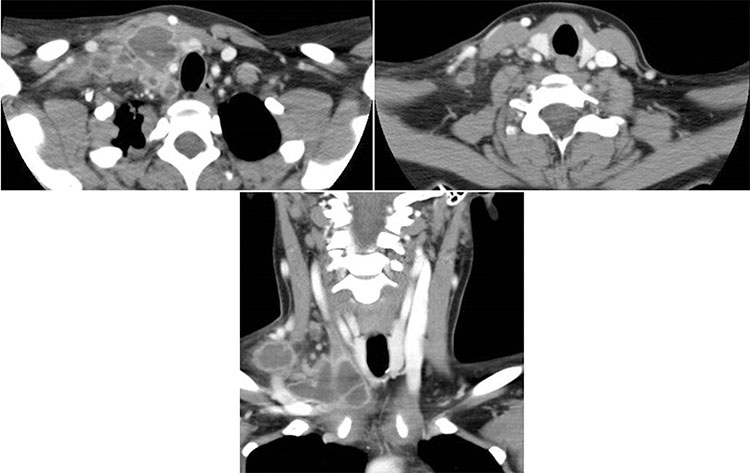

La presentación ganglionar cervical o escrofulosis, puede tener variadas complicaciones, dentro de ellas destacan el compromiso de los vasos del cuello, debido a la contigüidad de ellos en relación a los grupos ganglionares, pudiendo presentar tromboflebitis de los principales vasos (Fig. 3).

Mujer con baja de peso, dolor cervical y fiebre. Presentó durante el examen físico, adenopatías supraclaviculares palpables. Se realizó TC de cuello, destacándose en la región supraclavicular derecha y paratiroidea ipsilateral un conglomerado de adenopatías de aspecto necrótico, abscedadas, que medían hasta 7 cm de diámetro mayor. Se identificó un trombo en la vena yugular interna derecha.